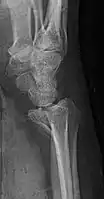

A Barton fracture is a type of wrist injury where there is a break of the front or back of the radius nearest the hand, resulting in the wrist being pushed out of place.[1] It typically occurs after falling on on top of a bent wrist.[2]

There exist two types of Barton's fracture – dorsal[3] and palmar, the latter being more common. The Barton's fracture is caused by a fall on an extended and pronated wrist increasing carpal compression force on the dorsal rim. Intra-articular component distinguishes this fracture from a Smith's or a Colles' fracture.